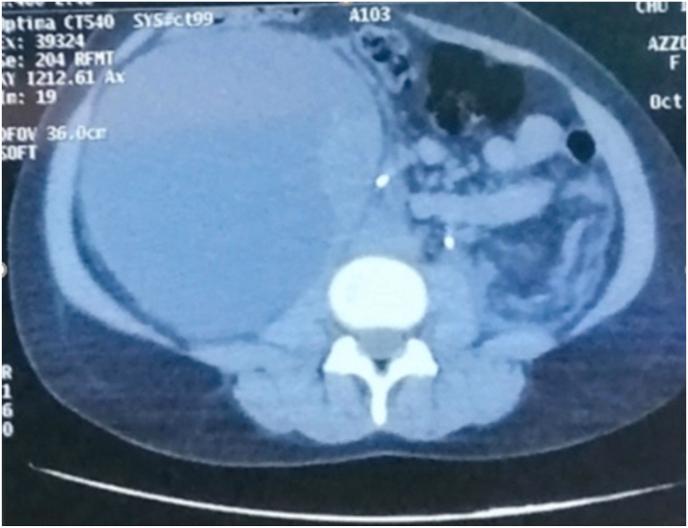

Spontaneous renal subcapsular effusion is a rare condition, diagnosis is suspected on ultrasound and confirmed by a computed tomography (CT) scan. Treatment options include mainly percutaneous drainage and surgery. Authors report the case of a young female patient treated at our department of Urology B, university hospital center Ibn Sina, Rabat, MOROCCO. The patient underwent a minimally invasive treatment approach, which yielded excellent results.